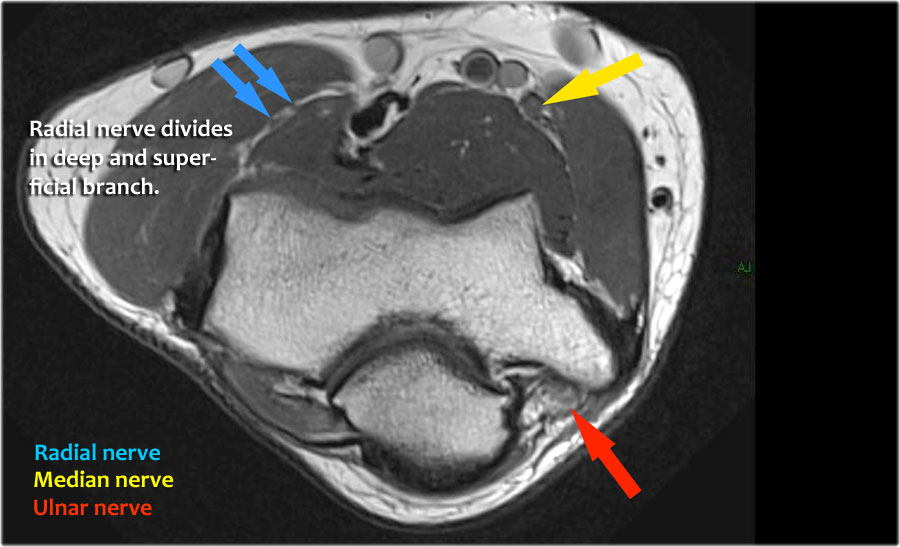

Radial nerve

Dây thần kinh quay có thể được xác định rõ nhất ở mức chỏm xương quay, nơi có thể quan sát thấy các nhánh nông và nhánh sâu trong ống xương quay (mũi tên).

This is a very consistent place to find the radial nerve.

Các nhánh quay sâu tạo thành thần kinh gian cốt sau xuyên qua cơ ngửa tại cung Frohse (mũi tên).